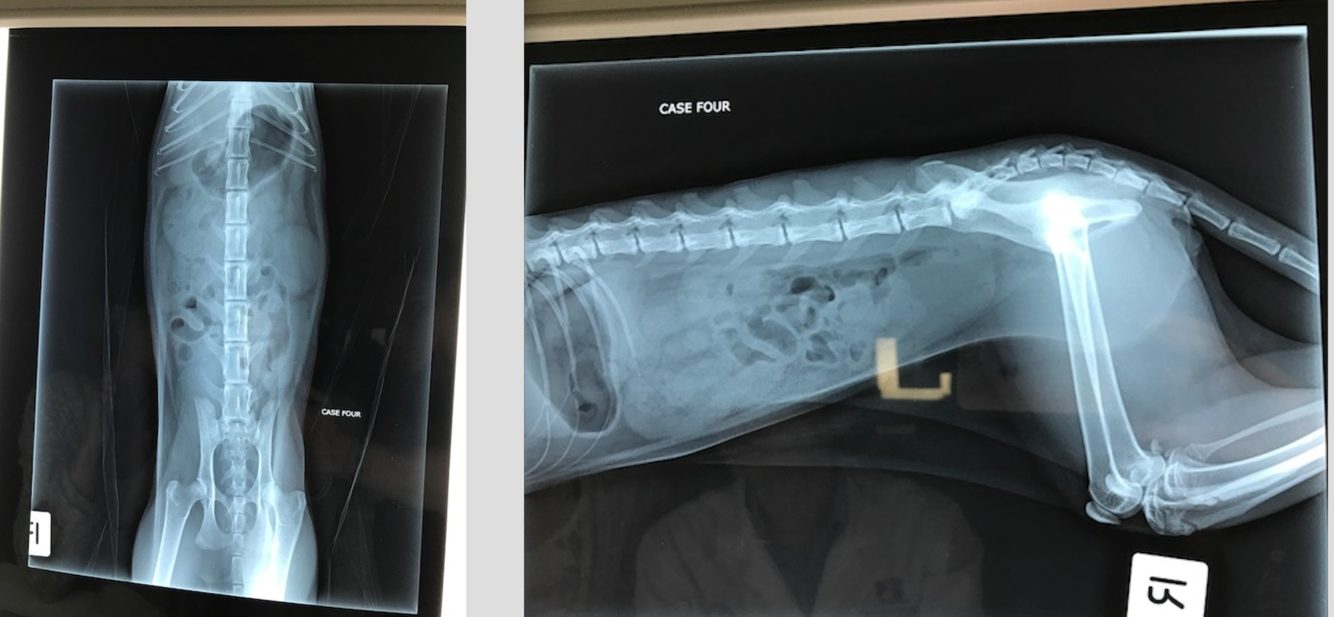

Pip

1 yo MN Ragdoll

Trodden by a horse

HR 138 RR 32 MM pale, lethargic, distended painful abdomen

DDX for decreased intraserosal detail?

What is most likely?

What structures can you see?

Are there any MSK abn?

What procedure has been performed? Describe how you would perform this study.

Can you namet he phases of the excretory urogram?

Is there a rupture of the urinary tract? What is the most likely cause of Pips loss of serosal detail?

Excretory urogram is used to visualize the kidneys and ureters while the other contrast studies are used to visualise the lower urinary tract.

AKA IV Pyelogram. An iodinated contrast agent such as iohexol is injected IV. Contrast agent is rapidly concentrated and excreted by the kidneys.

Nephrogram phase- the renal cortex and medulla opacity– rate of renal opacification and wash out of the contrast agent provides a rough indication of the filtraion ability of the kidneys.

The contrast agent is excreted by the nephrons and accumulates within the renal pelvis- the pyelogram phase. The size and shape of the renal

pelvis can be assessed

Cystogram- Almost immediately, the contrast agent will pass down the ureters, and into the

urinary bladder, producing a ‘cystogram’.